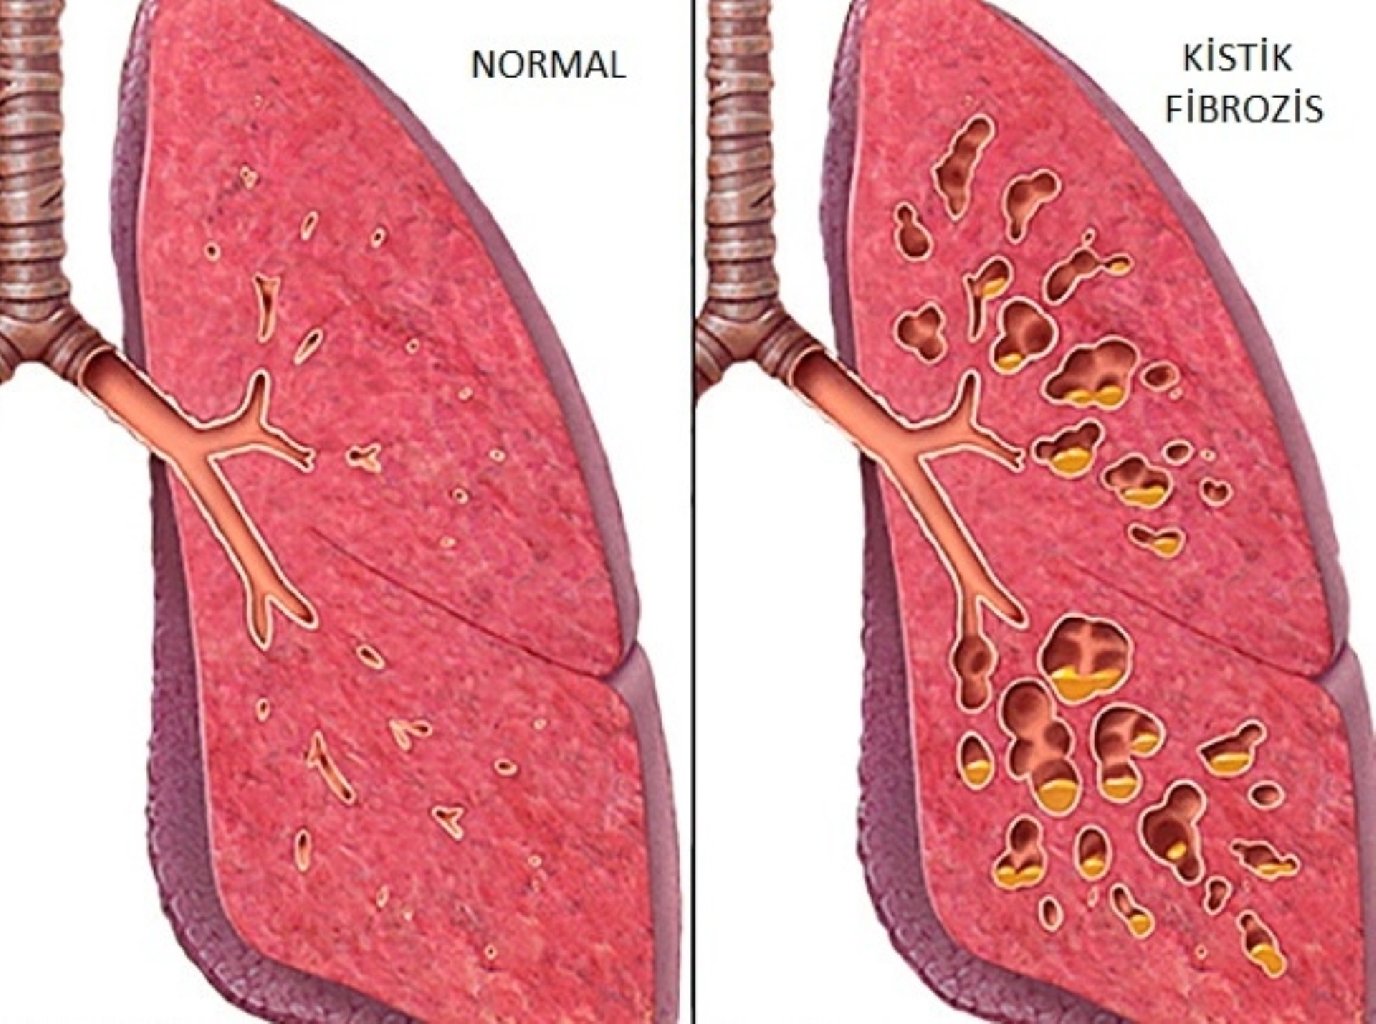

Bronxopulmoner Sistem Üzərində Təsiri: Kistik fibroz, solunum yollarında qatı, yapışqan balğamın yığ ...